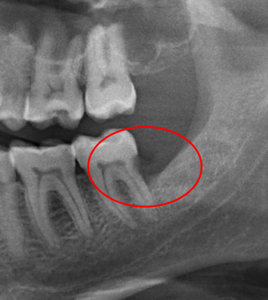

У меня зуб болит. Я его лечила 3 года назад. Мне поставили штифт в декабре 2015, он опять заболел, сделали снимок, оказалось, что он был плохо пролечен. Сняли пломбу, смогли пройти только один канал, во втором канале материал, третий мне врач не смог пройти (инструмент упирался в десну). Тогда еще врач сказал, что этот зуб только удалять, я не согласилась на удаление и мне его просто перекрыли пломбой, теперь опять побаливает.

В зубе имеется перфорация, к сожалению, такой зуб спасти и сохранить невозможно.